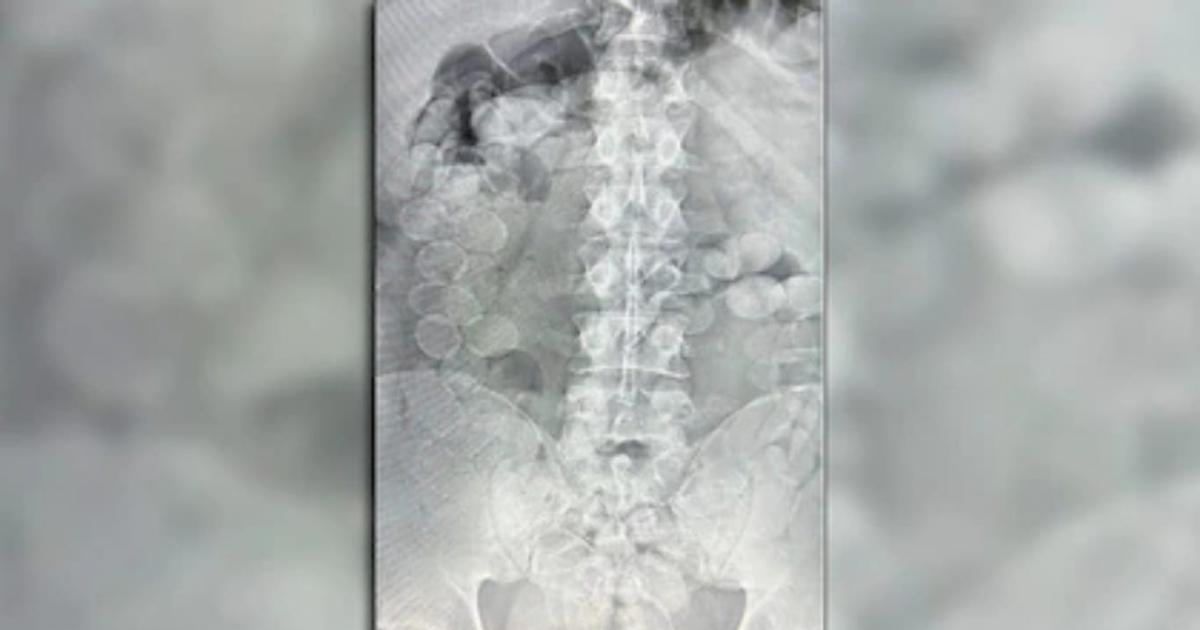

Ante la situación, ambos hombres comenzaron a evidenciar malestar físico y terminaron admitiendo que habían ingerido cápsulas con estupefacientes. De inmediato fueron trasladados a un centro de salud de la zona, donde estudios confirmaron la presencia de cuerpos extraños en sus organismos.

Con el correr de las horas, los involucrados expulsaron un total de 185 cápsulas que contenían cocaína. El peso conjunto de la sustancia superó los 2,4 kilos y presentaba un alto nivel de pureza, según se determinó en los análisis posteriores.